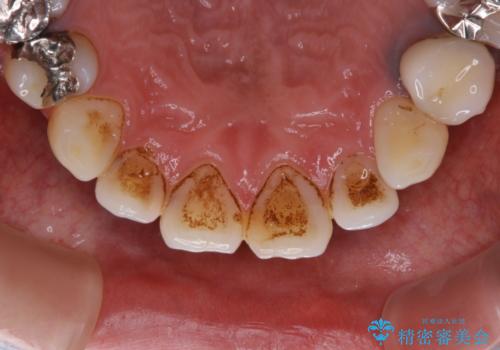

- 虫歯治療を始める前に、まずはしっかり汚れを取りたいとのことで来院されました。歯石やステインが分厚く付着していたため、PMTC60分コースを行いました。

歯の表面に、茶色く色が残っている所がありますが、これは詰め物の変色によるものです。以前に、CR(コンポジットレジン)による虫歯治療がされています。

CRは経年的劣化や、着色してしまうことがあります。PMTCでクリーニングを行うと、古いCRが目立つことがあるため、気になる際は詰め替えを行います。

茶色くなっている部分が、着色なのか、劣化なのか、虫歯によるものなのかは判別が難しいことがあります。そのため、定期的にPMTCを行うことで状態の確認が的確に行えます。